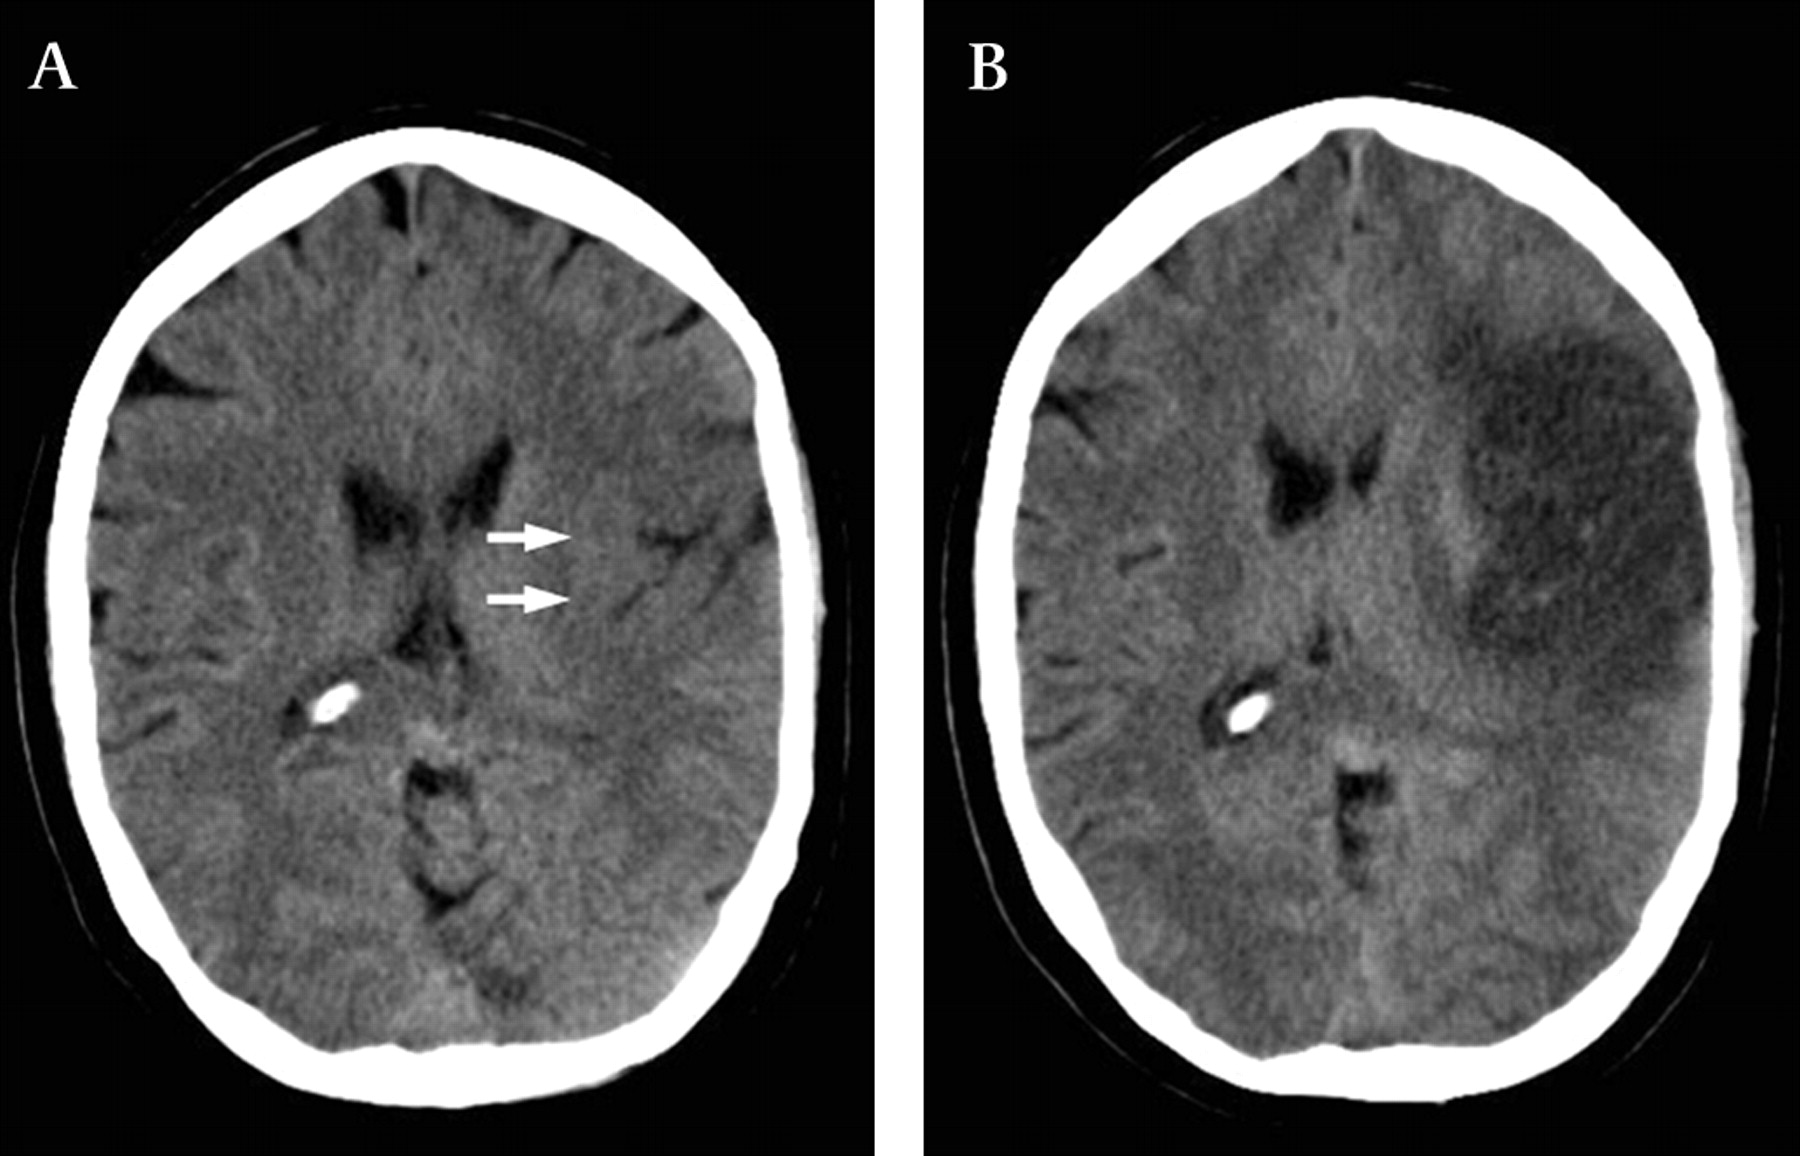

1. 신속한 평가 및 진단: 뇌경색 초기증상과 징후를 신속하게 인식하는 것은 적시에 개입하고 환자 결과를 개선하는 데 필수적입니다. 의료 전문가는 NIHSS(National Institutes of Health Stroke Scale)와 같은 도구를 사용하여 잠재적인 뇌경색 환자를 신속하게 평가하고 컴퓨터 단층 촬영(CT) 스캔 또는 자기 공명 영상(MRI)을 포함한 진단 테스트를 시작하여 진단을 확인하고 유형을 결정해야 합니다.

2. 즉각적인 치료: 뇌경색이 진단되면 뇌 손상을 최소화하기 위해 가능한 한 빨리 치료를 시작해야 합니다. 특정 치료는 뇌출혈 유형에 따라 다릅니다(허혈성 또는 출혈성) 다음과 같이 분류할 수 있습니다.

• 허혈성 뇌졸중(혈전이 뇌로 가는 혈류를 차단하여 발생)의 경우 증상이 시작된 후 처음 4.5시간 이내에 조직 플라스미노겐 활성화제(tPA)와 같은 혈전 용해 약물을 투여하면 결과를 크게 개선할 수 있습니다. 경우에 따라 기계적 혈전 제거술과 같은 혈관 내 절차를 수행하여 혈전을 제거하고 혈류를 회복할 수도 있습니다.